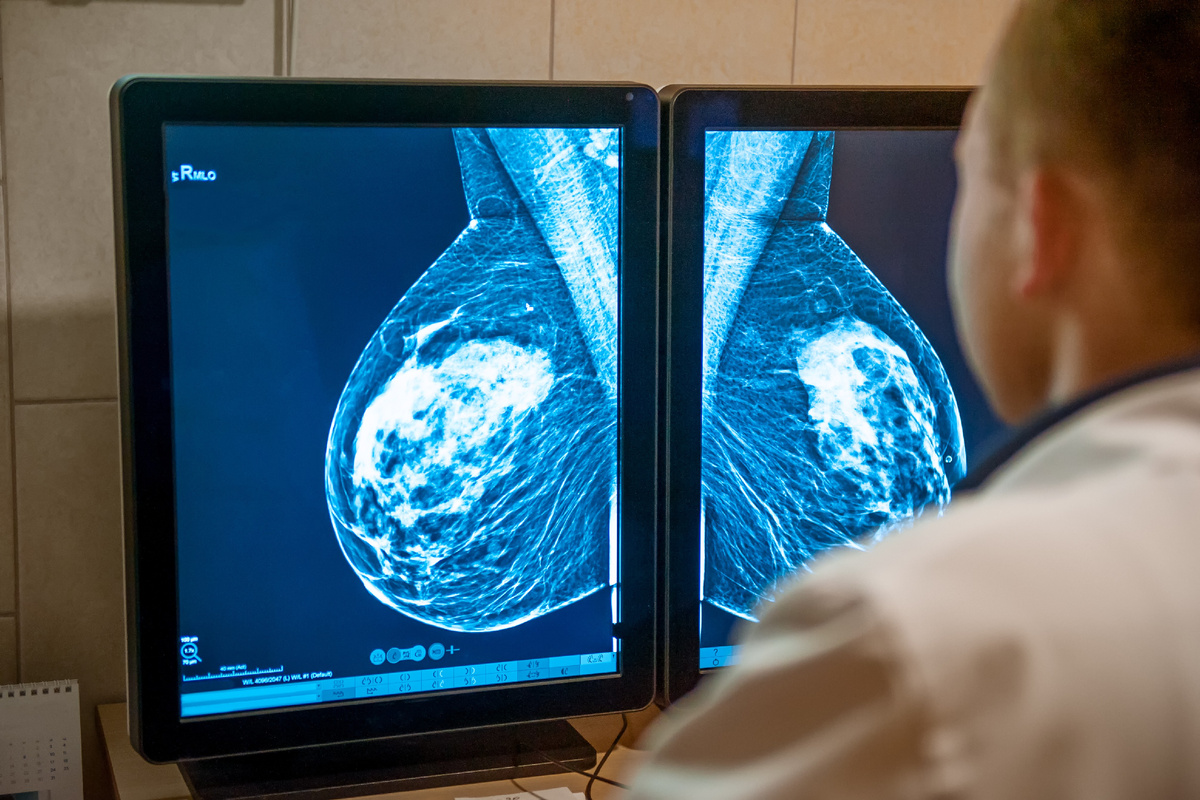

18 августа во всем мире отмечают День исследования рака молочной железы. Для врачей это не только важная дата календаря, но и напоминание о том, как стремительно развивается наука и какие возможности открываются для диагностики и лечения.

В последние годы исследователи уделяют особое внимание молодым женщинам. Для клинической практики открываются новые перспективы ранней диагностики. Это позволяет значительно снизить риски и увеличить шансы на полное излечение.